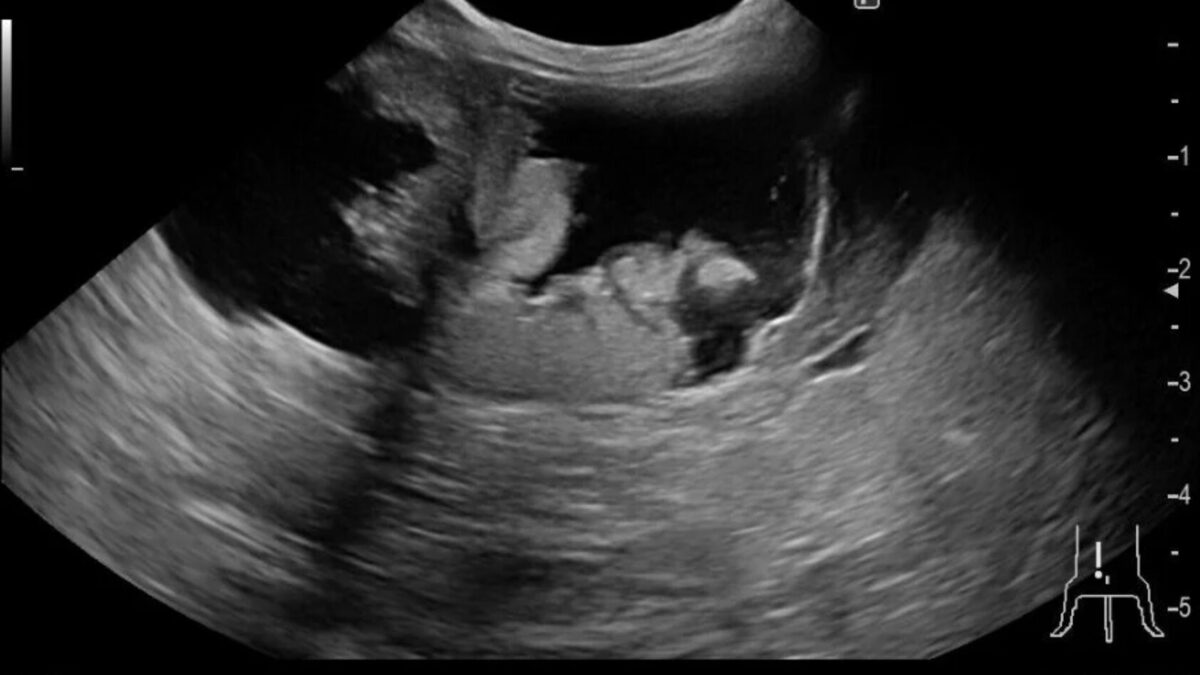

症例は8歳7ヶ月のうさぎで体調が悪い、食欲が落ちているとの主訴で来院しました。

超音波検査をしたところ子宮に水がたまっており、子宮の腫瘍が疑われたため摘出手術を行いました。

子宮は拡張しており炎症が起きていました。